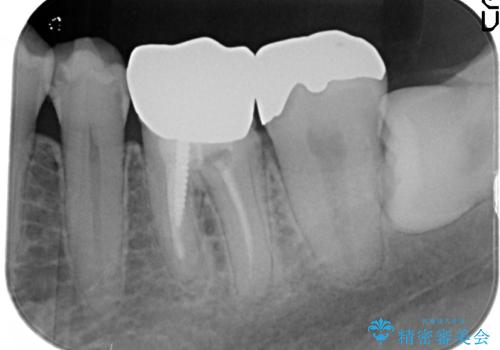

左下6はメタルクラウン、左下7はメタルアンレーがあり、左下5には虫歯がありました。

左下5はセラミックインレー修復、左下6,7はオールセラミッククラウンにて修復していくこととしました。

左下6に関しては、メタルコアをファイバーコアへのやりかえ、やりかえの際根管の汚染が強かったため根管治療からやりなおすこととなりました。